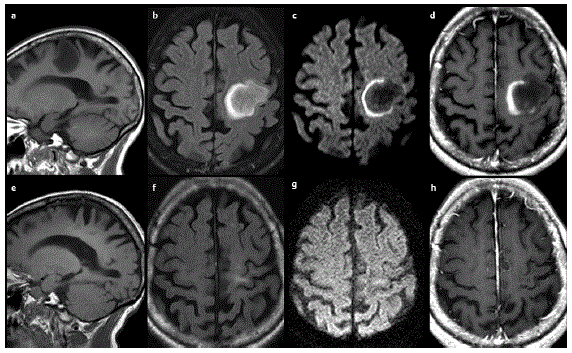

CASO 1. Mulher de 40 anos deu entrada em urgência devido a crises convulsivas e déficit motor. Durante acompanhamento médico, teve as seguintes imagens no diagnóstico e 1 ano após diagnóstico, sem ter sido submetida a qualquer tratamento específico.

a: sagital T1; b: axial t2 flair; c: axial difusão; d: axial T1 contrastada. e, f, g, h: são as imagens correspondentes às superiores 1 ano após.

Em relação ao caso, assinale a alternativa CORRETA.